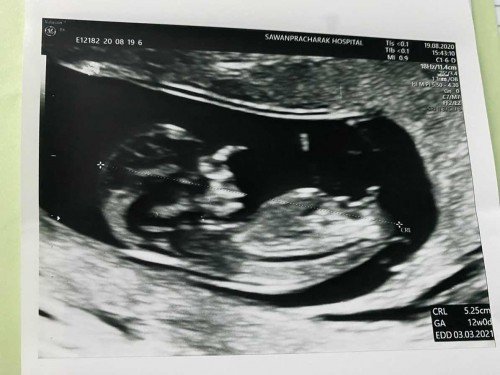

ความหวังตั้งไว้อยากได้ ผญ แต่หมอบอก ยาวมาเลยนะแม่ จู๋อีกแล้ว อิแม่ห๊ะลั่นห้องเลยจ้า😂🤣 ซาวตอน 12w จ้า ปัจจุบัน 14w จ้า

12w เห็นจู๋แล้วไวมากค่าาาแม่ บ้านนี้12wยังมองไม่เห็นเลยใช้วิธีเจาะเลือดหาโครโมโซมค่ะ ได้ผช.เหมือนกานนน👶🏻